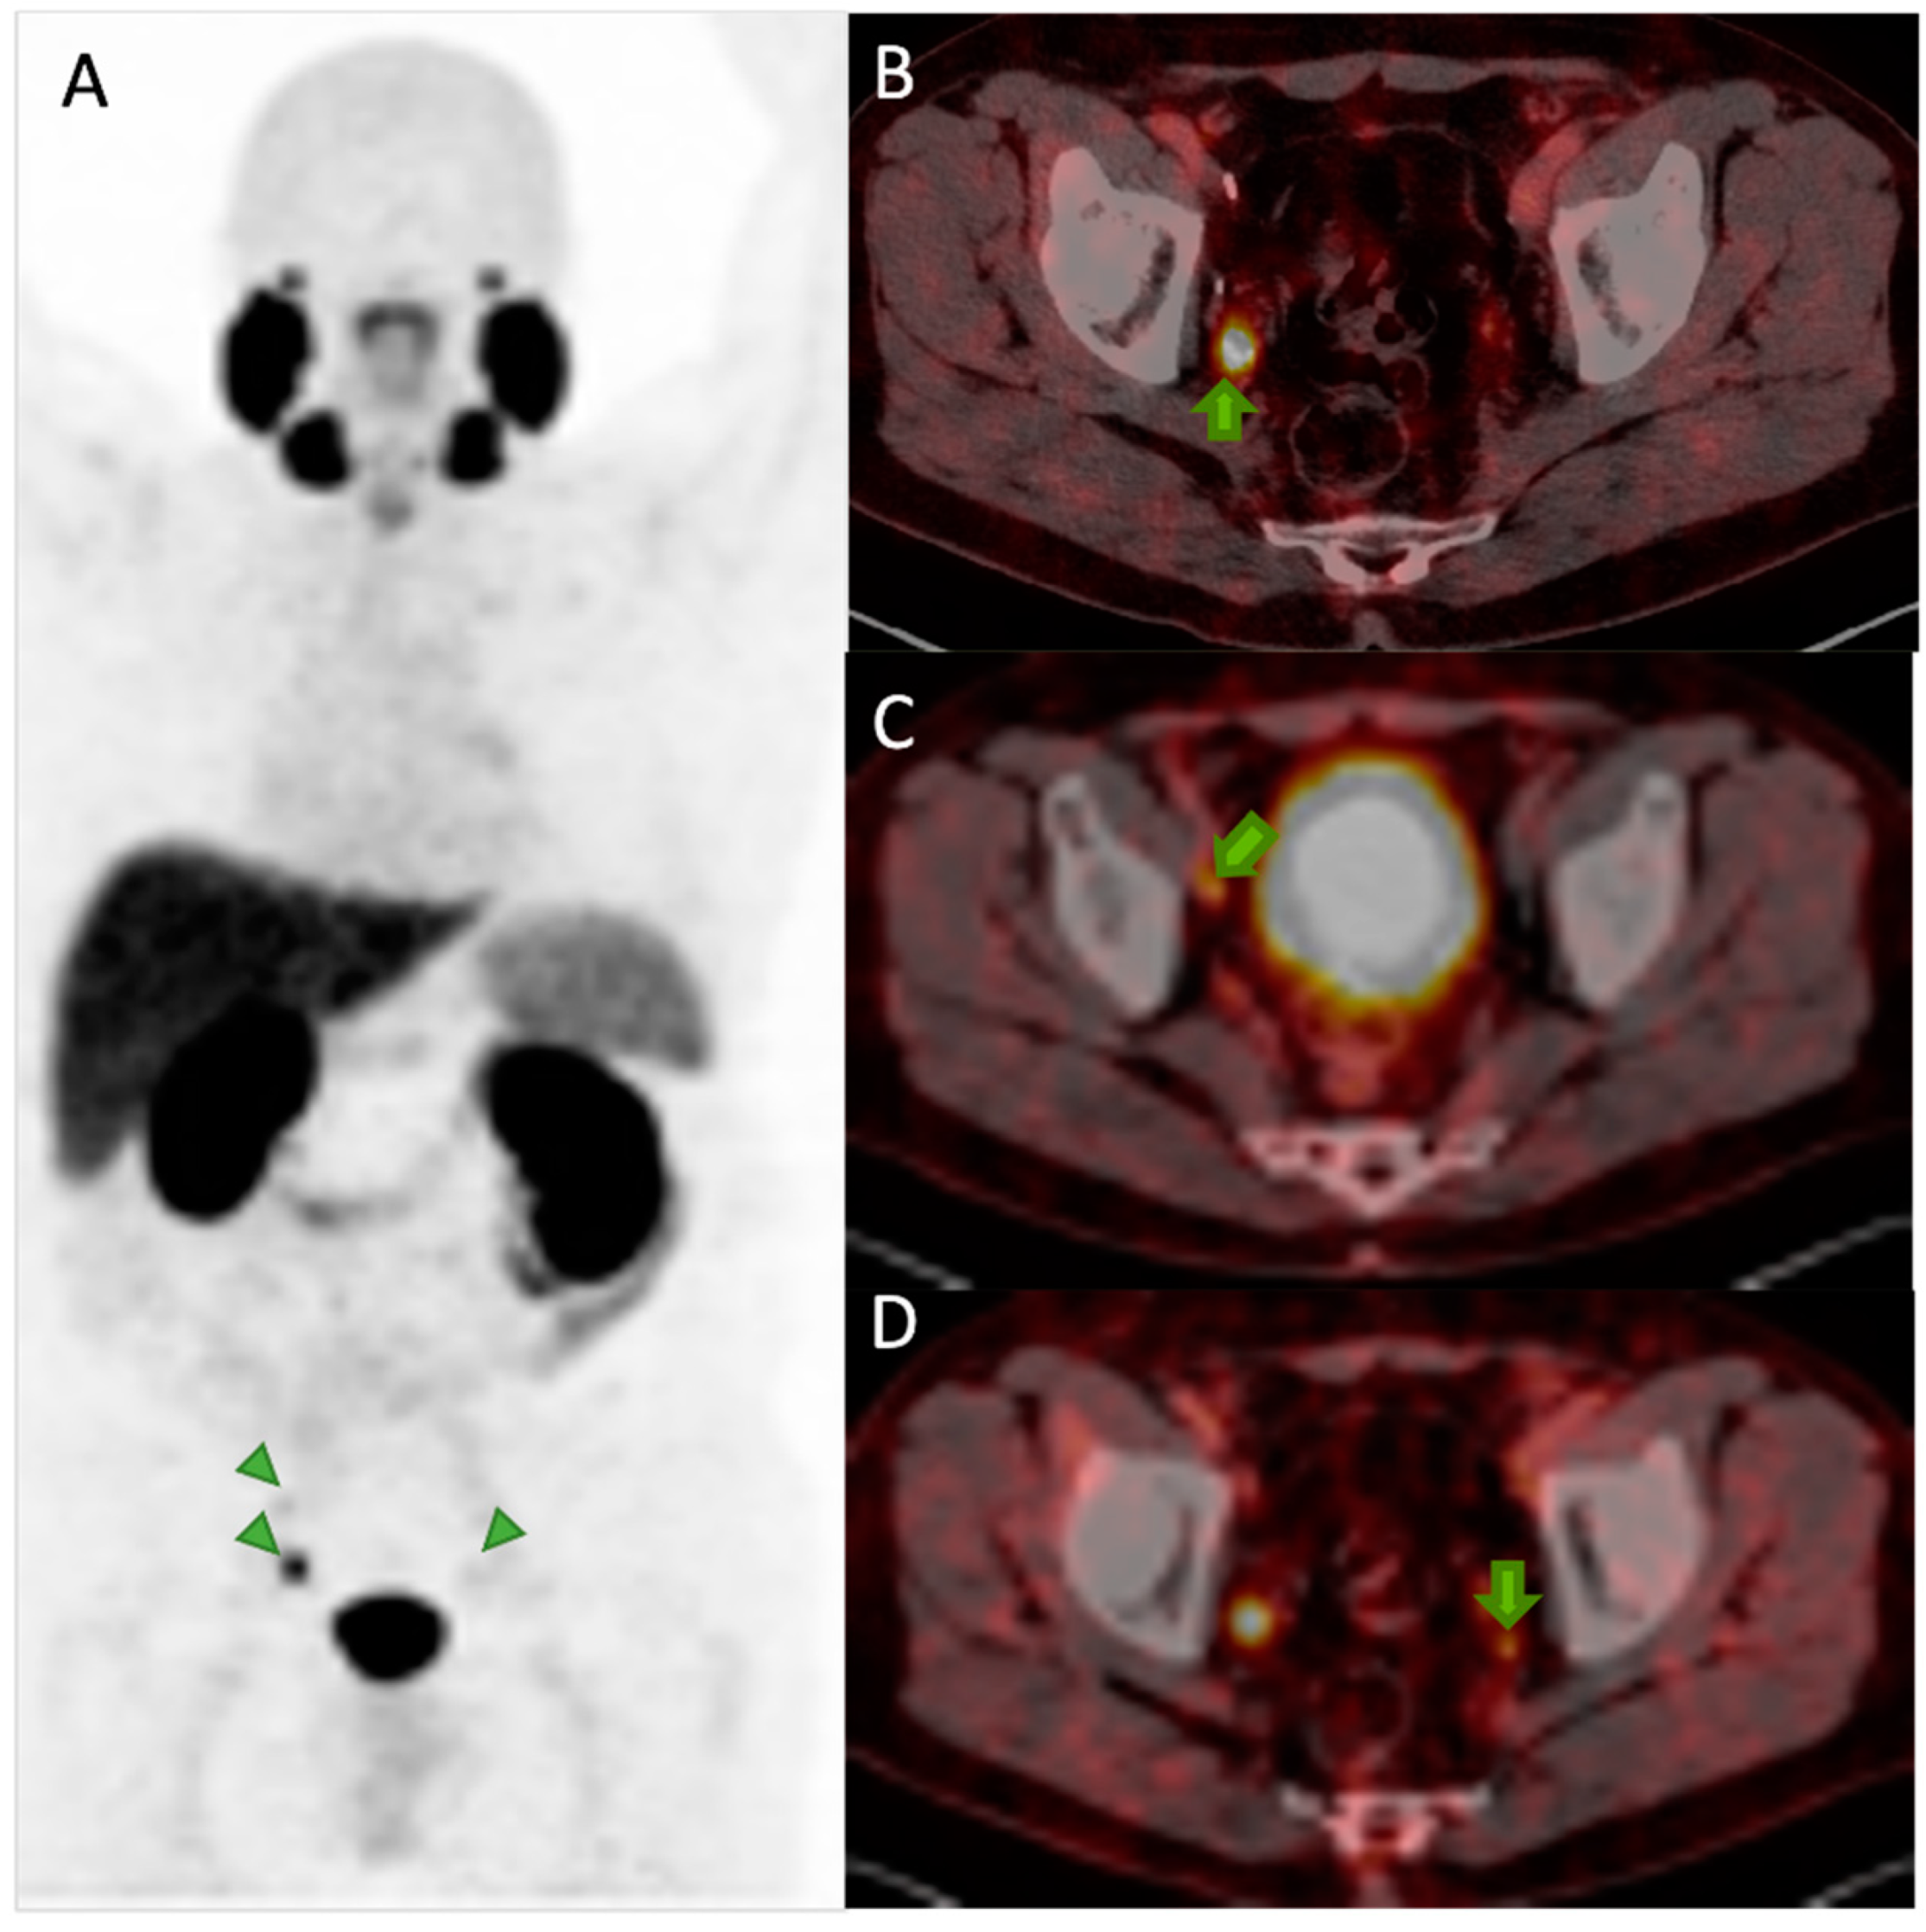

6. Diagnosis with PSMA PET/CT

6.3. Detection of Biochemical Recurrence